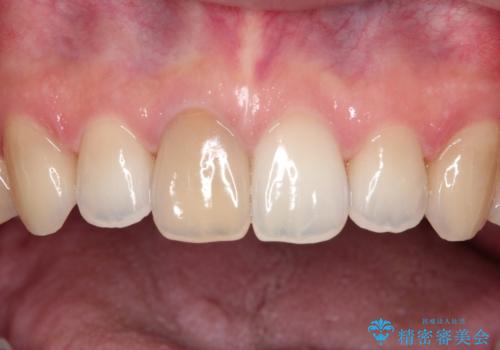

【前歯の被せ物】オールセラミッククラウン(エクセレント)

- 空隙歯列と前歯の変色を主訴に来院されました。

空隙歯列を矯正にて改善した後に歯冠修復を行なっております。

上顎前歯は根管治療後にオールセラミッククラウン(エクセレント)で修復を行なっております。

オールセラミッククラウン(エクセレント)では技工士さんの立ち会いのもと、より審美的な修復が可能です。